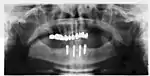

Success or failure of implants depends primarily on the thickness and health of the bone and gingival tissues that surround the implant, but also on the health of the person receiving the treatment and drugs which affect the chances of osseointegration. The amount of stress that will be put on the implant and fixture during normal function is also evaluated. Planning the position and number of implants is key to the long-term health of the prosthetic since biomechanical forces created during chewing can be significant. The position of implants is determined by the position and angle of adjacent teeth, by lab simulations or by using computed tomography with CAD/CAM simulations and surgical guides called stents. The prerequisites for long-term success of osseointegrated dental implants are healthy bone and gingiva. Since both can atrophy after tooth extraction, pre-prosthetic procedures such as sinus lifts or gingival grafts are sometimes required to recreate ideal bone and gingiva.

Biomechanical considerations

The long-term success of implants is determined in part by the forces they have to support. As implants have no periodontal ligament, there is no sensation of pressure when biting so the forces created are higher. To offset this, the location of implants must distribute forces evenly across the prosthetics they support.[29]: 15–39 Concentrated forces can result in fracture of the bridgework, implant components, or loss of bone adjacent the implant.[30] The ultimate location of implants is based on both biologic (bone type, vital structures, health) and mechanical factors. Implants placed in thicker, stronger bone like that found in the front part of the bottom jaw have lower failure rates than implants placed in lower density bone, such as the back part of the upper jaw. People who grind their teeth also increase the force on implants and increase the likelihood of failures.[16]: 201–208

When a more exacting plan is needed beyond clinical judgment, the dentist will make an acrylic guide (called a stent) prior to surgery which guides optimal positioning of the implant. Increasingly, dentists opt to get a CT scan of the jaws and any existing dentures, then plan the surgery on CAD/CAM software. The stent can then be made using stereolithography following computerized planning of a case from the CT scan. The use of CT scanning in complex cases also helps the surgeon identify and avoid vital structures such as the inferior alveolar nerve and the sinus.[32][33]: 1199